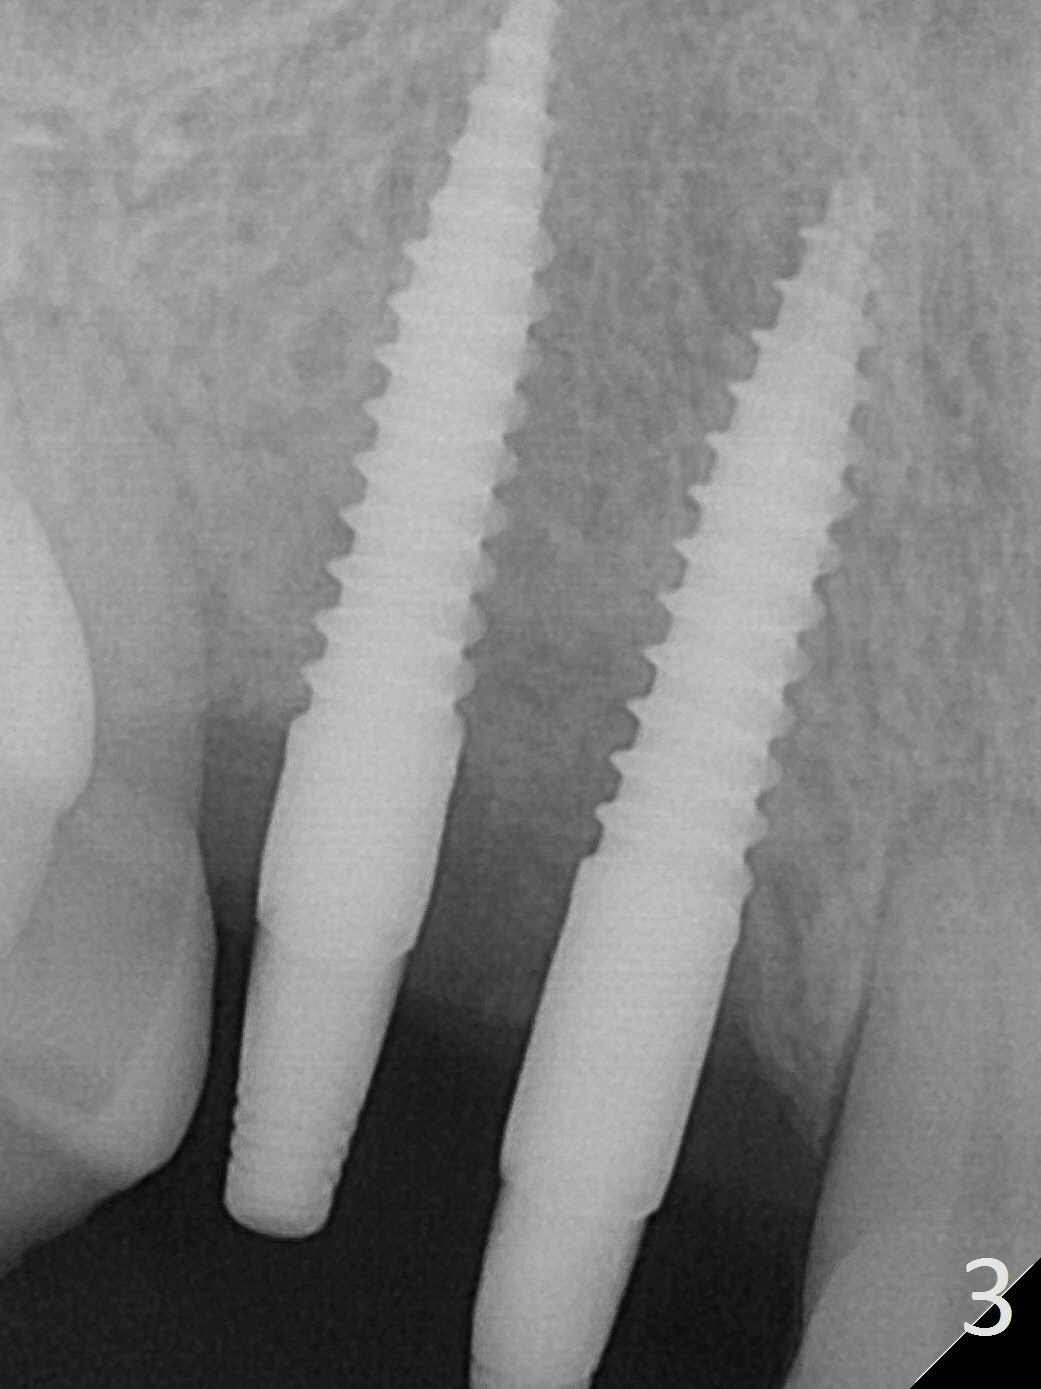

There is no bone loss 3 months postop (Fig.3, probably due to the hard bone).